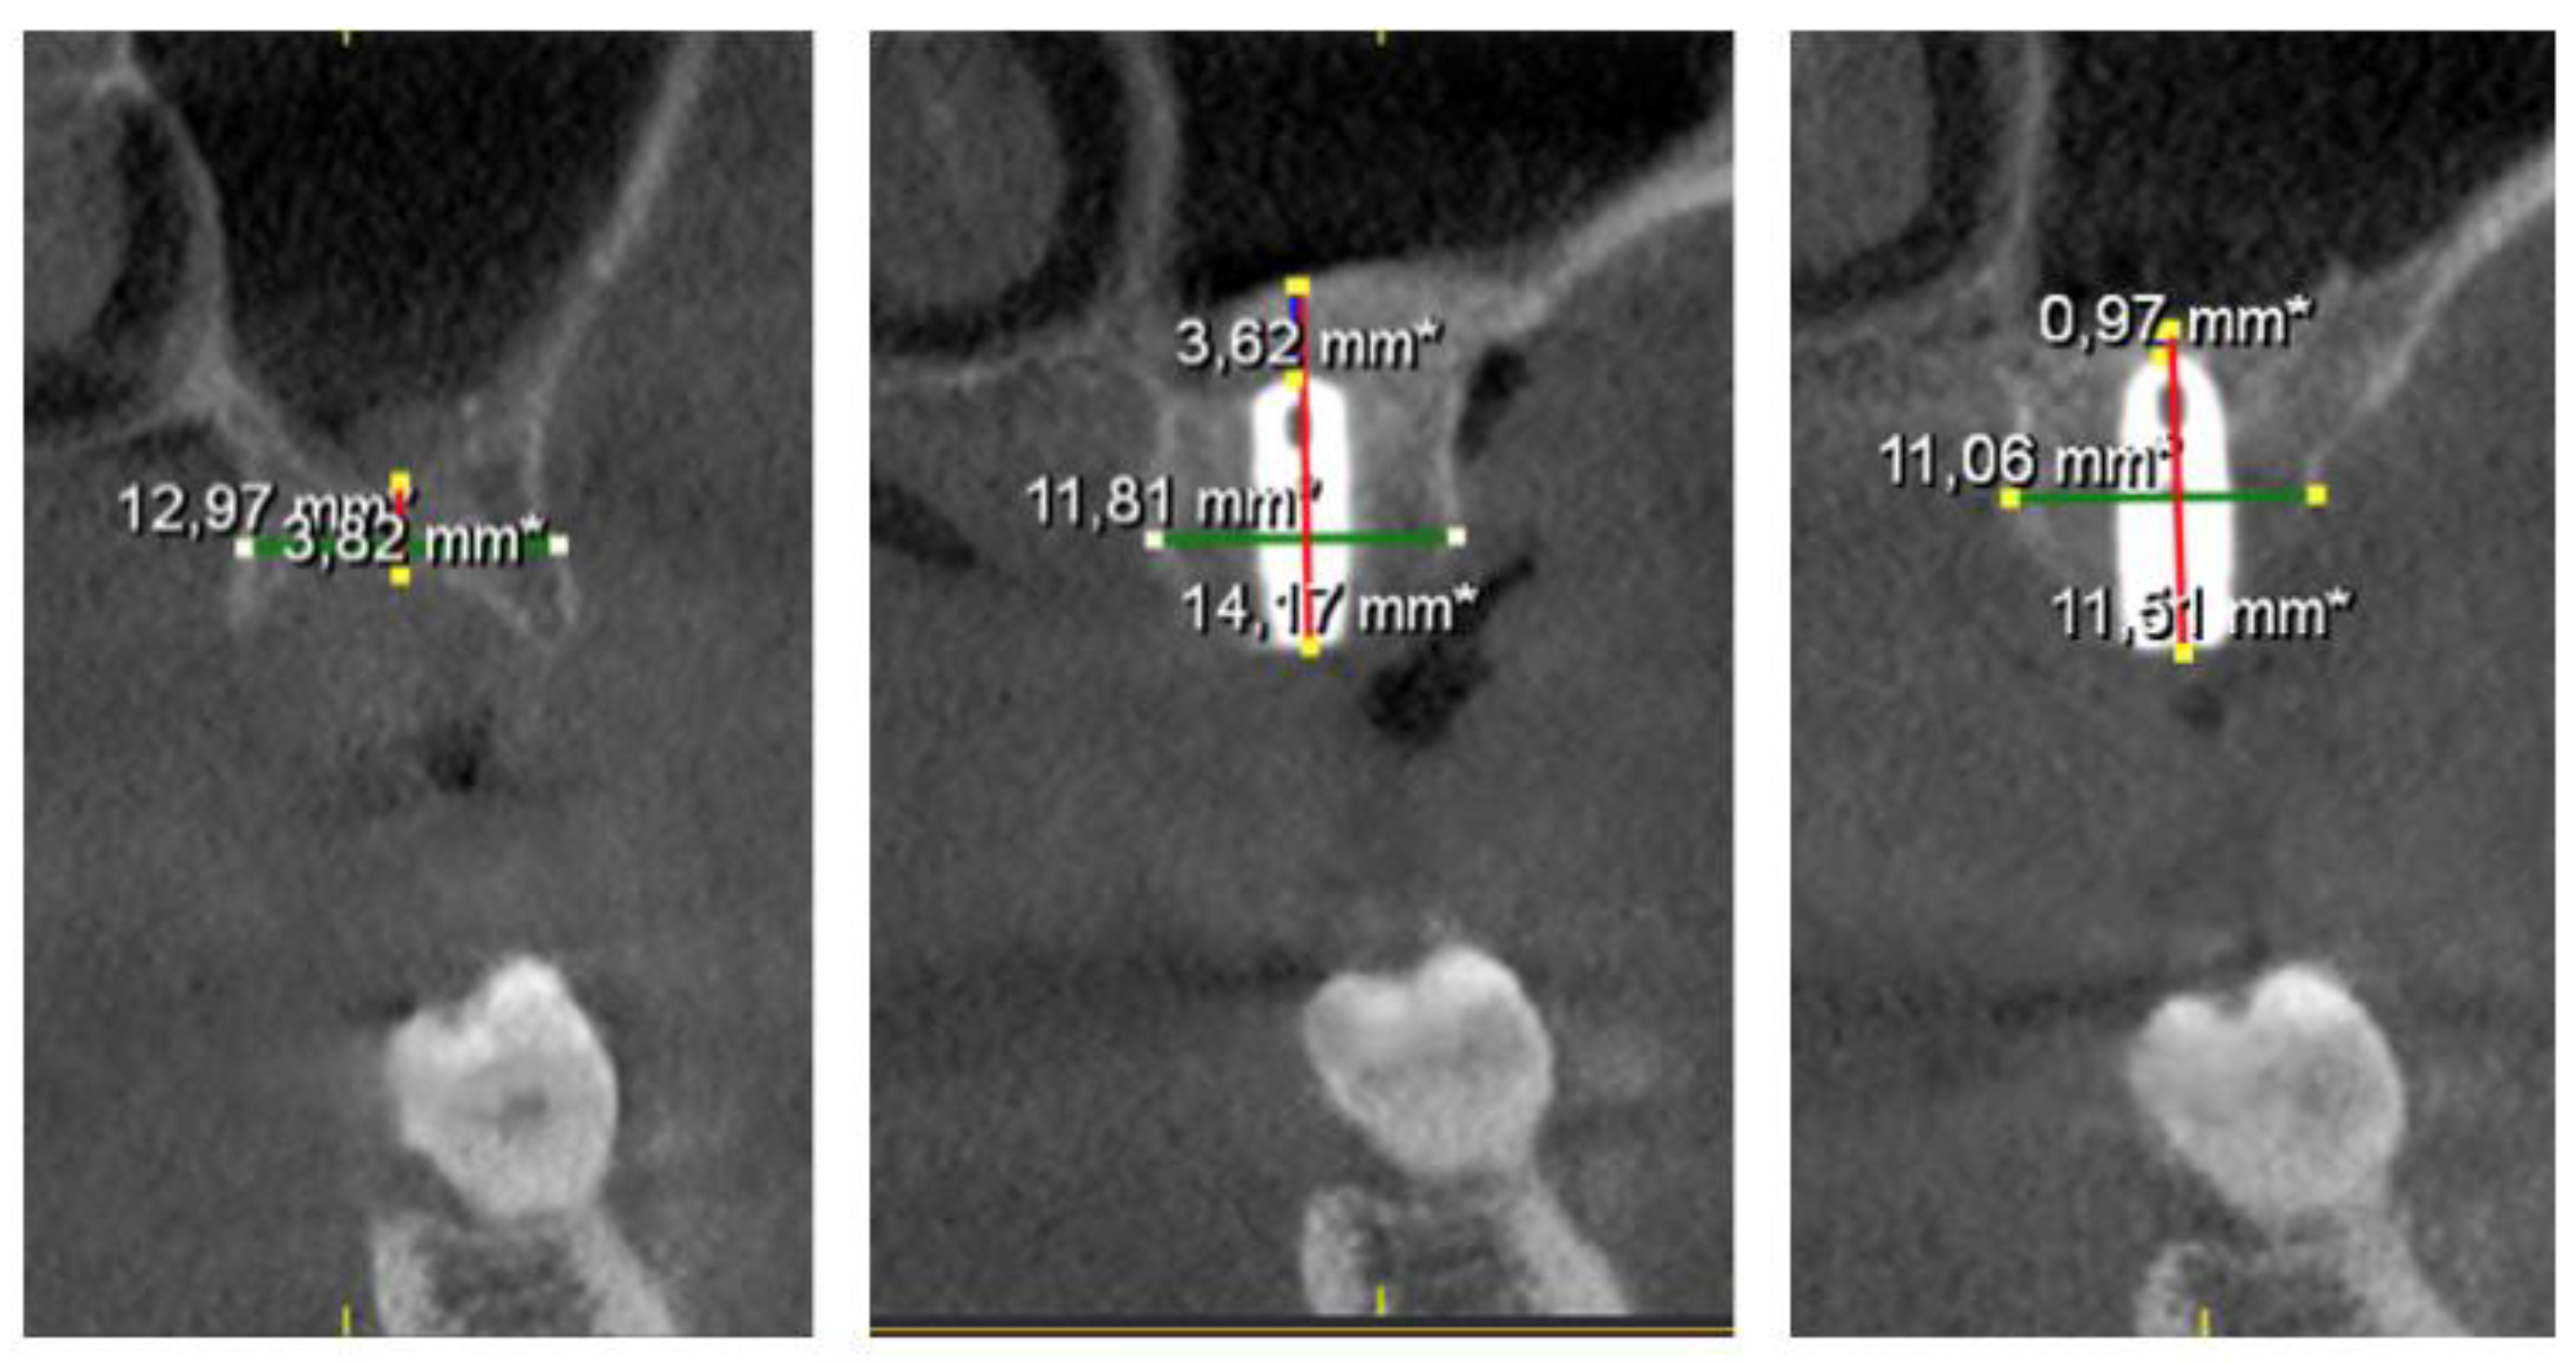

In the radiographic study, the following parameters were recorded: RBH: Residual bone/ available bone height, measured parallel to the implant axis, from the bone crest to the sinus floor; RBW: Residual bone width, measured in the vestibular-palatal direction; ABG: Apical bone gain. Distance from implant apex - most apical bone, measured along the axis of the implant. This value was considered as zero if the Schneiderian membrane was left in contact with the apex of the implant. All CBCT cross-sections were collected and analyzed by the same doctor and measurements were made by taking landmarks of the antagonist quadrant and adjacent structures (Figure 4).

Figure 4. Cross sections of the CBCT with the measurements made at the different moments of the study (T0, T1, T2).

Preprints 101155 g004

The mean RBH preoperatively (T0) was 5.70 ± 0,95 mm (IR: 3.47 to 8.40), immediately after surgery RBH (T1) was 12.36 ± 1.20 mm and after 12 months follow up RBH (T2) was 11.45 ± 0.94 mm (Figure 5). The results of RBH variations are shown in Table 3.

After transcrestal sinus lift surgery, a mean considerable increase of 6.65 ± 1.06 mm was achieved immediately after surgery (T0 – T1). A limited physiological contraction of the bone graft (0.90 ± 0.49 mm) was observed during the healing period (T1 – T2) shown in (Figure 5). As the sample follows a normal distribution, a comparison t-test for related samples was used to analyze these differences, shown in Table 4.